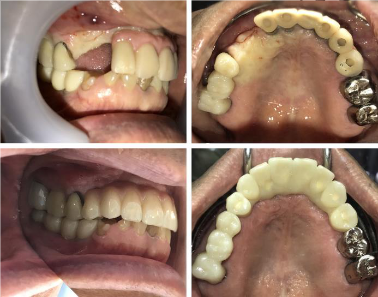

咬合力が強い方なので、日常的な歯の噛みしめ癖や歯ぎしりの強さに、歯が負けてしまったのだと思います。歯ぎしりの影響か、12年前にインプラントを入れた前歯(ハイブリッドセラミック)も、かなり摩耗して形が変わっています。

通常は、2本歯がなくなったところには2本のインプラントを入れますが、摩耗して形が変わってしまった歯もきれいにするために、「インプラントは1本だけ埋入して、以前のインプラントとつなげることで強度を保ちつつ、全体をきれいにする」ことになりました。インプラントが1本で済むので、約25万円ほど患者様のご負担額が少なくなります。

後日来院された際に、「すぐに新しいかぶせ物に慣れて、普通に食事をしています。」とのことでした。かぶせ物にはより丈夫なジルコニアを使用したので、摩耗もかなり防げると思いますが、歯とインプラントを守るために、就寝時用のマウスピースを使っていただくことになりました。